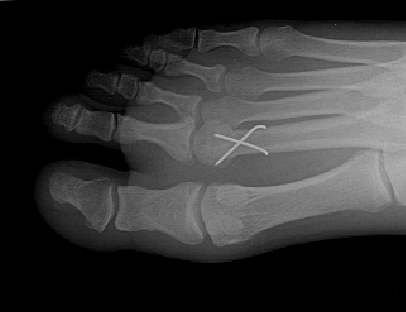

We recently had a patient present to our institute for continued pain to his right foot six months after plantar plate repair in the right second metatarsophalangeal joint (MPJ). A review of the operative report and computed tomography (CT) scan found that the patient had a second metatarsal plantar condylectomy with Kirschner wire fixation. Unfortunately, he developed avascular necrosis of the second metatarsal head with significant bone resorption. He presented to our institute to discuss his surgical revision options. This condition is difficult to treat and often frustrating.

For select younger patients who present with associated significant bone or loss of the entire metatarsal head, it is important to consider surgical options that try to maintain a proper metatarsal parabola. One of the newer and more technical advancements in the treatment of second MPJ avascular necrosis is transplant of the second metatarsal head with an osteochondral allograft. Fixation and proper alignment are essential in such cases.

Metatarsal head resurfacing (HemiCAP, Arthrosurface) can serve as an excellent option in cases of avascular necrosis with minimal bone shortening. The Morris taper design allows for excellent bone apposition and also results in a solid fixation with immediate range of motion potential. If there is extensive bone loss and a low demand situation, we have found an arthroplasty with a tendon graft space technique to be an excellent option. We will typically place a peroneal tendon allograft in the resection site and then pierce it with a retrograded K-wire from the tip of the toe into the MPJ. We then spin the tendon into a ball filling the empty joint space before advancing a Kirschner wire into the metatarsal. We have found this technique an effective method for limiting shortening at the resection site.